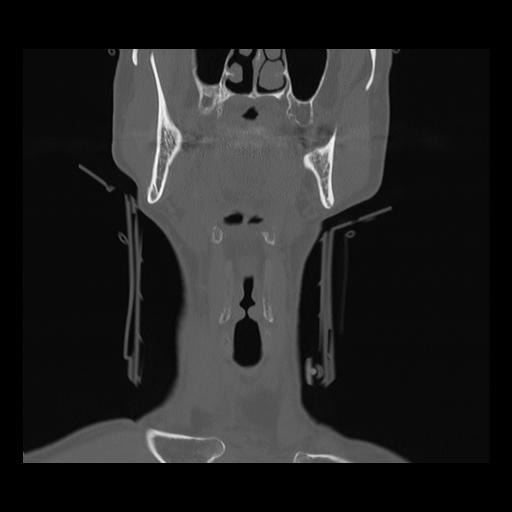

16 HUESO,,Coronal,2.000,HUESO,Coronal,